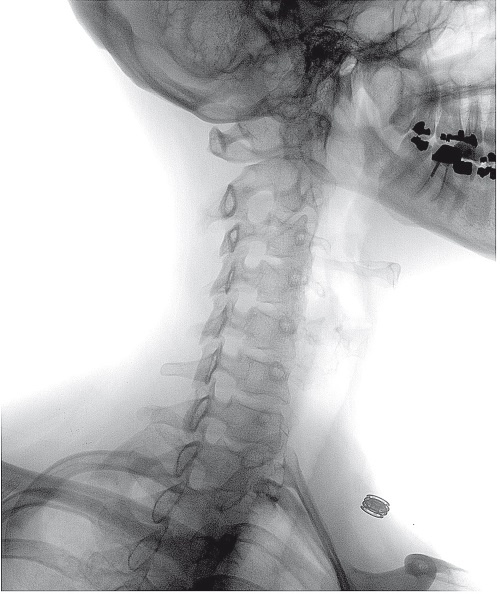

Иллюстрация к книге — Ни кошелька, ни жизни. Нетрадиционная медицина под следствием [i_014.jpg]